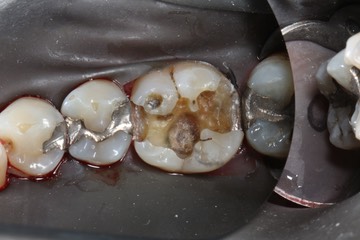

Larry Fujioka #19 amalgam removal